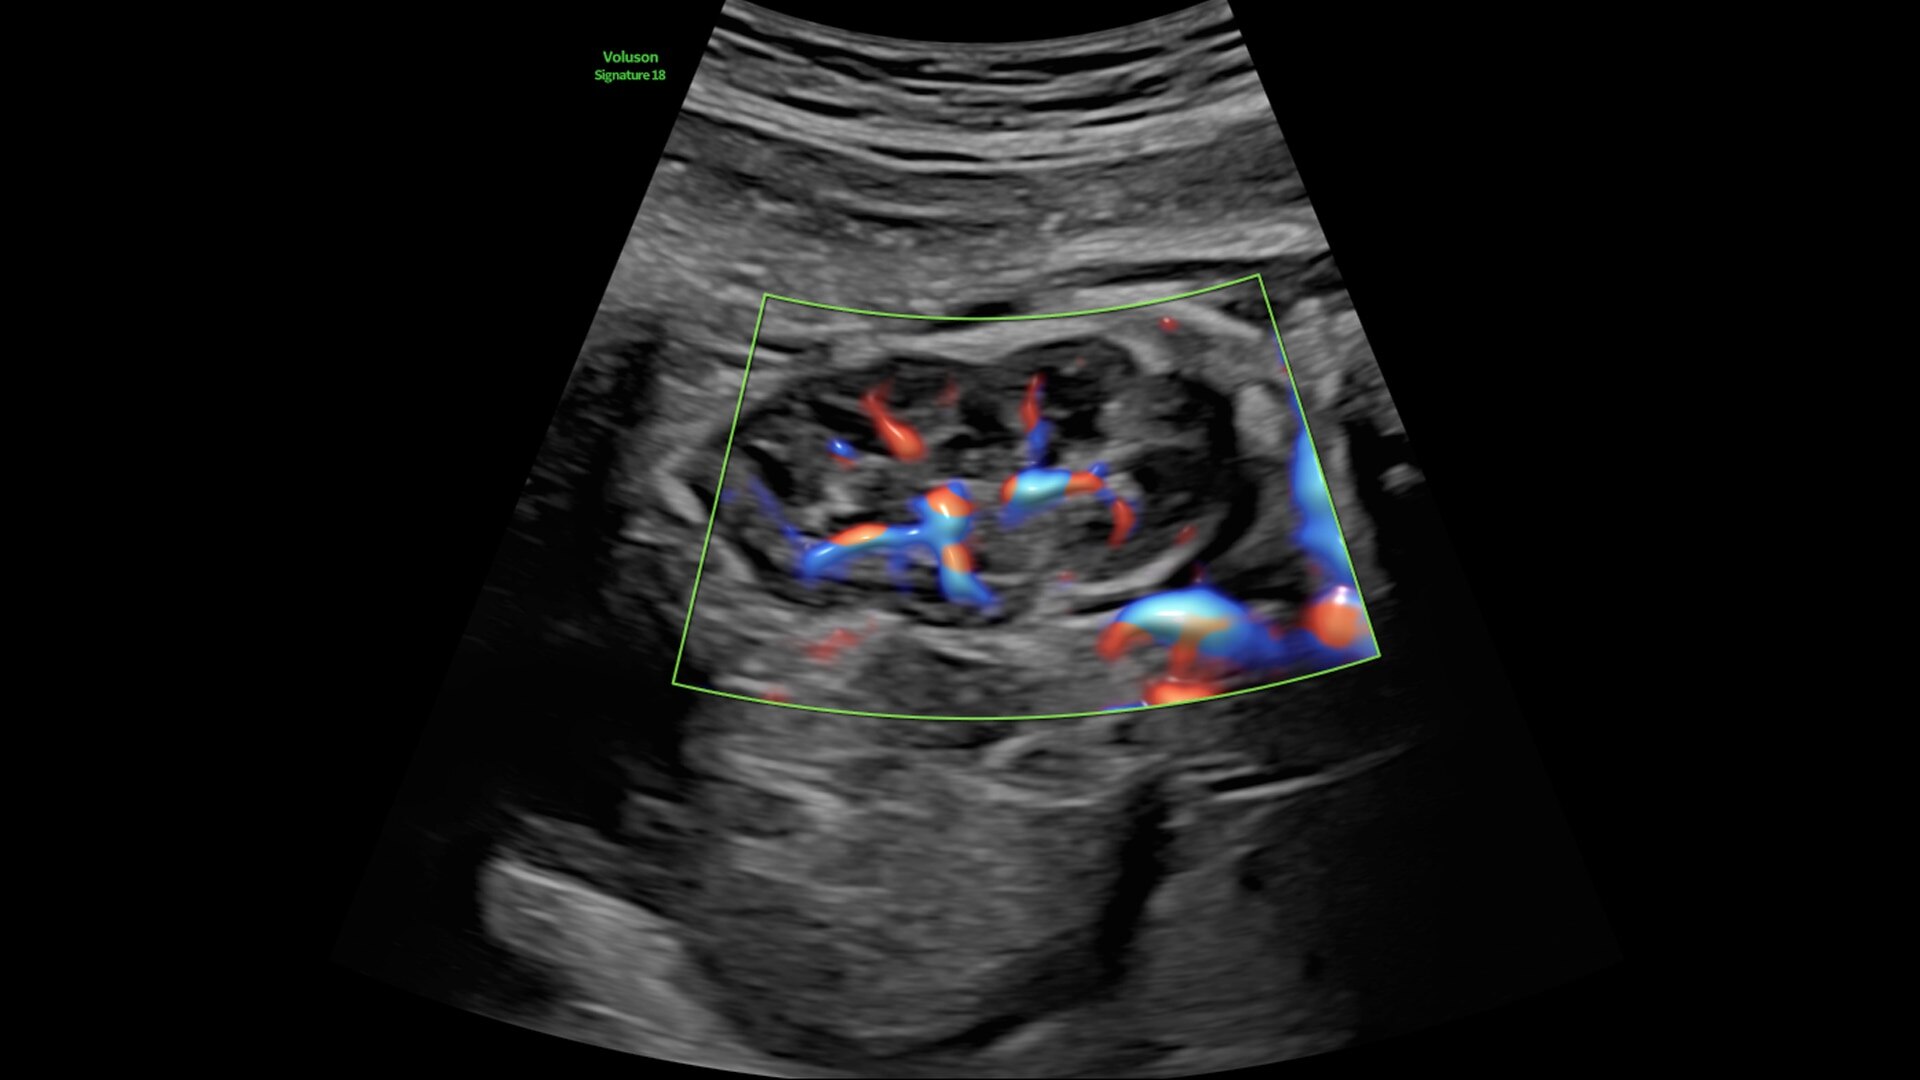

Fast, easy 3D-like blood flow visualization

Next level color Doppler delivers exceptional sensitivity for easy, fast visualization of blood flow, revealing even the tiniest vessels.

3-radiantflow-clinical-image-ci-en